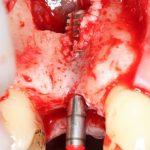

Вторая особенность — мы не адаптируем и не обрабатываем костный блок invitro, а фиксируем его так, как есть:

после чего обрабатываем — доводим до окончательной формы альвеолярного гребня: